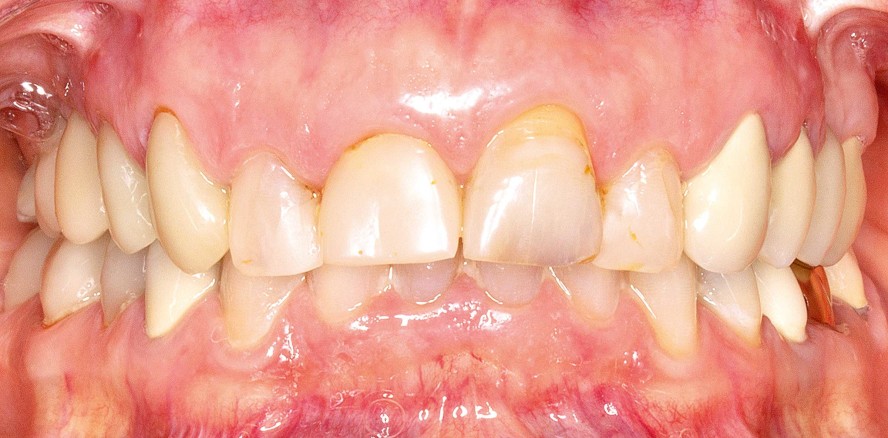

In unsere Praxis kam eine 53-jährige Patientin mit Problemen an ihren Frontzähnen: Bei der Untersuchung zeigten sich insuffiziente Füllungen an den Zähnen 12 bis 22 sowie ein uneinheitlicher Gingivaverlauf an 12 und 11. Eine chirurgische Anpassung lehnte die Patientin ausdrücklich ab. Zudem war der Schneidekantenverlauf stark abradiert und nicht harmonisch. Die Patientin litt unter der mangelnden Ästhetik, traute sich kaum zu lächeln und wünschte sich dementsprechend eine Versorgung, die ihr ein neues Lächeln schenkte. Es wurde geplant, die vier Zähne in einer Sitzung final mit jeweils einer Krone zu versorgen. Aufgrund der Zahnfarbe C3 fiel die Entscheidung, sie mit IPS e.max, einer Lithiumdisilikatkeramik, zu versorgen. Dieses Material würde für eine sehr natürliche Ästhetik sorgen, was in diesem Fall höchste Priorität hatte. Für die Versorgung wurde dem klassischen CEREC-Protokoll gefolgt: Die Zähne wurden exkaviert, aufgebaut, präpariert und anschließend mit der Primescan digital abgeformt. Im virtuellen Modell wurden die auto­matisch eingefügten Präparationsgrenzen noch leicht korrigiert und intraoral abgeglichen. Anschließend wurden die Kronen direkt am Stuhl kon­struiert. Auf diese Weise konnte die Patientin durchaus mitentscheiden und sich dadurch noch besser mit ihrer neuen Versorgung identifizieren. In diesem Fall ging es vor ­allem um die Darstellung der inzisalen Kanten, die im natürlichen Gebiss nicht vorhanden waren.